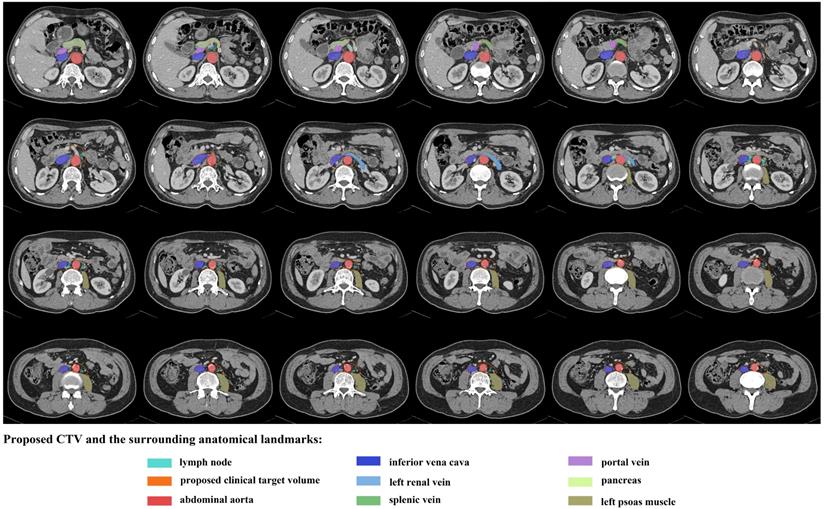

Figure 3

An illustration of proposed CTV contours based on template CT (from standard patient) with 5 mm slice thickness.

J Cancer Image

To better describe the distribution of the LNs, longitudinally, we divided the area into celiac level (from the celiac trunk to the appearance of SMA), SMA level (from the appearance of SMA to the appearance of the left renal vein) and the region below the SMA (from the appearance of the left renal vein to the bifurcation of the AA). A number of 30, 17 and 201 LNs were seen in the celiac level, SMA level and the region below the SMA, respectively. All the LNs were located below the level of 1.0 cm above the appearance of CA, rendering it an acceptable upper border. As for the caudal edge, 235 (94.76%) LNs were above the bottom of vertebra L3.

Horizontally, in the celiac level, 93.33% of LNs, except two postcaval LNs, were located within an expansion of 1.5 cm on the CA (bounded by the IVC and portal vein on the right, 1.5 cm beyond the left aspect of the AA on the left, the anterior surface of AA posteriorly and the pancreatic body or splenic vein anteriorly). In the SMA level, 94.12% of LNs were within 1.5 cm on the left side of SMA, and all the nodes were behind the anterior edge of the SMA, anterior to the front edges of the vertebral bodies, and left to the left surface of IVC. In the level beneath the SMA, 98.51% of LNs appeared medial to the lateral surface of the LPM, and all the LNs were behind the anterior surface of the left renal vein or adjacent to the anterior surface of the aorta, left to the right border of IVC and anterior to the vertebral or the anterior edge of the LPM. Table 3 summarised the locations of the PALNs in relation to the aforementioned landmarks.

CTV modification and dosimetric analysis

As shown in Figures 2 and 3, the proposed CTV began at the level 1.0 cm above the CA, then downed to the bottom of vertebra L3. The CTV in the CA level was an area within the 1.5 cm expansion on the CA. Beneath the CA level, the posterior border was the posterior edge of AA in the SMA level and the ventral surface of the vertebral and the front edge of LPM in the region below. The anterior edge was the front end of the SMA in the SMA level and retracted to the anterior surface of the left renal vein, and was set at 0.5 cm anteriorly to the AA below the left renal vein. The right border of the CTV in the SMA level was the connecting line between the anterior of SMA and the left border of IVC, and reached to the right border of the IVC in the region below the SMA. Meanwhile, the left border of the CTV in the SMA level was set at 1.5 cm left to the SMA and to the lateral border of the LPM in the region below. The proposed CTV could cover all of the LNs in 83.08% of the patients and encompassed 92.74% of the studied LNs.